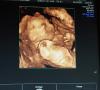

28-29 хорошо все видно и не страшненький, как инопланетянин. Клиника «Я здорова!» на Коломенской